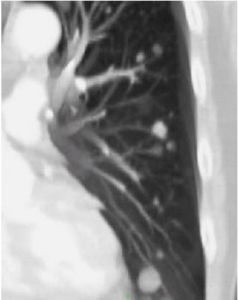

原發性肺動脈高壓症,一種原因不明,以自發性肺動脈壓進行性升高為特徵,常伴右室肥大和右心功能不全表現的心血管疾病。基本病變為肺小動脈的硬化、狹窄、栓塞或叢狀變。青壯年起病,常呈進行性加重。臨床表現

原發性肺動脈高壓可發生於任何年齡,患者可出現呼吸困難,易於疲勞,胸部不適,病情進一步發展可出現胸痛及勞力後暈厥,有時擴張的肺動脈可壓迫左側喉返神經而出現聲音嘶啞,最後可發生右心衰竭,嚴重者可猝死,體格檢查可見頸靜脈搏動出現增大的A波,右室肥厚時可見胸骨左緣3,4肋間心臟搏動,叩診心界擴大,聽診肺動脈瓣區第二心音亢進,第二心音分裂,部分患者可有收縮早期噴射音,肺動脈瓣區收縮期噴射性雜音的存在提示肺動脈擴張造成了肺動脈開口的相對性狹窄,Graham-Steel雜音提示肺動脈瓣相對關閉不全,如肺動脈高壓引起右心室擴大則出現三尖瓣的相對關閉不全,可聽到三尖瓣區的收縮期雜音。

1.肺動脈高壓的典型症狀、體徵及X線,超聲心動圖表現。必要時經右心導管直接測定肺動脈及右心壓力。2.除外由心、肺疾患誘發的繼發性肺動脈高壓後方能診斷本病。